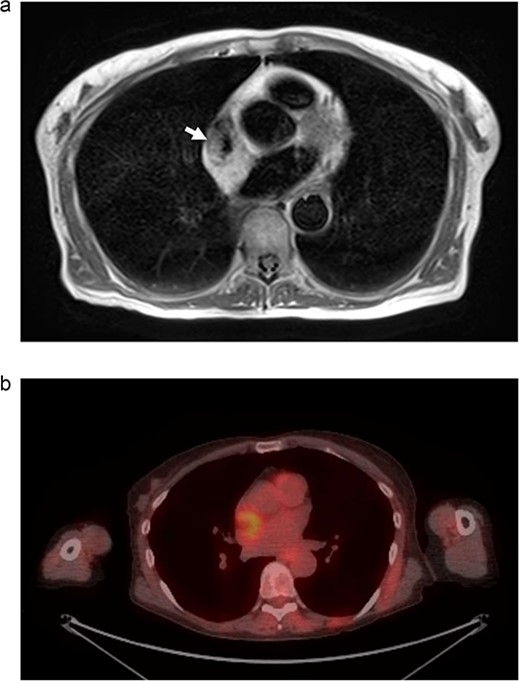

We present another rare case of a hibernoma occurring just a few months later. A 63-year-old woman with history significant for HTN, COPD, GERD, ETOH abuse, and a 54-pack year tobacco use experienced continued weight loss of 70 lbs in the last 5 years. She underwent extensive workup for malignancy, which included MRI of the chest. MRI showed a 3.0 x 3.1 cm tumor circumferentially involving the superior vena cava at the atriocaval junction. This mass was hyperintense on T1 and T2-weighted images (Fig. 3a). Transesophageal echocardiogram was performed, and the mass was not appreciated. PET showed increased FDG uptake in the mass area without evidence of extracardiac disease (Fig. 3b). The recommendation was made for surgical resection.

(a) MRI chest. Mass represented by white arrow. (b) PET/CT. Uptake is demonstrated in the mass associated with the SVC and right atrium.